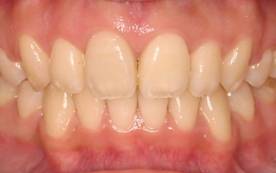

前歯のみの矯正治療 ワイヤー矯正

上の前歯が一部逆に生えていました

4か月後、前歯のかみ合わせのみの矯正ですので、短期間で終了しました